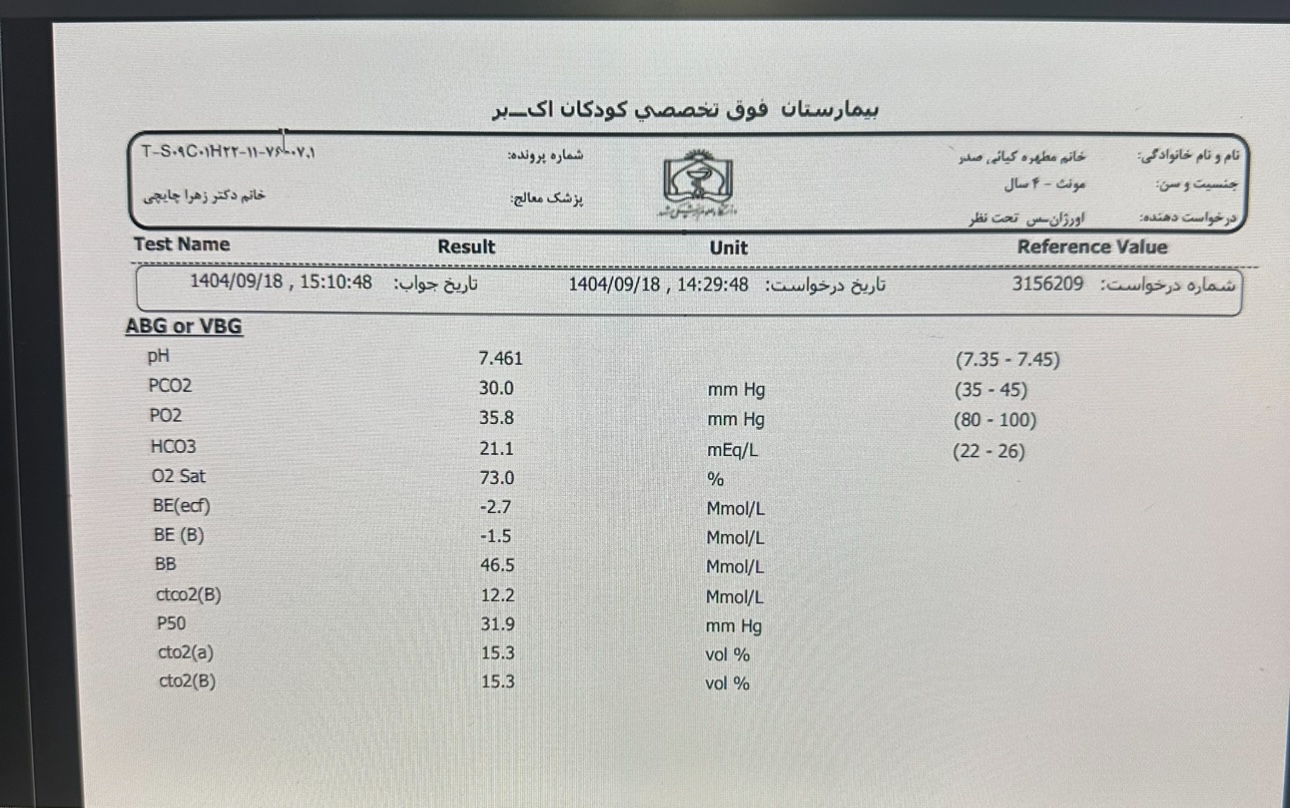

Other:

Other:

Other:

Other: